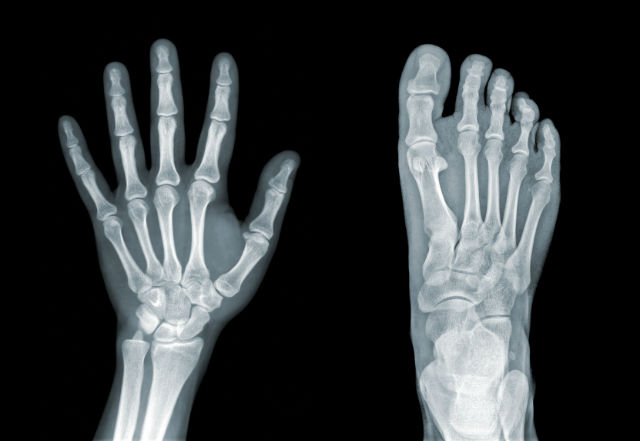

The term “bone fat” refers to the fat content of bone marrow, the tissue found within our bones. Bone marrow is home to a variety of cells, including blood and immune cells. It also has fat content, which can vary in concentration over time, and may be altered by lifestyle factors.

Dr. Styner notes that research has observed that more bone fat is produced by mesenchymal stem cells within the bone as a person ages, and it is hypothesized that this increased production of bone fat is a factor in older people’s susceptibility to bone fractures.

An earlier study, published in 2013 in the journal Radiology, analyzed the bone fat content of over 100 obese adults (between the ages of 19 and 45) with no other health issues, and found that the individuals with higher levels of muscle and liver fat also had higher levels of bone marrow fat. The researchers concluded that high levels of fat in the bone marrow increased an individual’s risk of bone fracture.

Lead author Dr. Miriam Bredella summarizes, “bone marrow fat makes bones weak. If you have a spine that’s filled with fat, it’s not going to be as strong.”